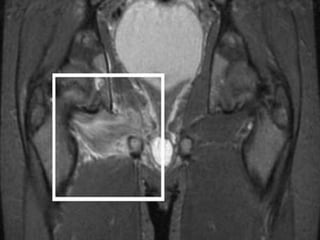

Focus of abnormal signal intensity in middle

one third of proximal femoral epiphysis.

Pelvic tilt toright with medial hip joint space narrowing

• 82.

Focus of abnormalsignal intensity in middle one third of proximal femoral epiphysis.